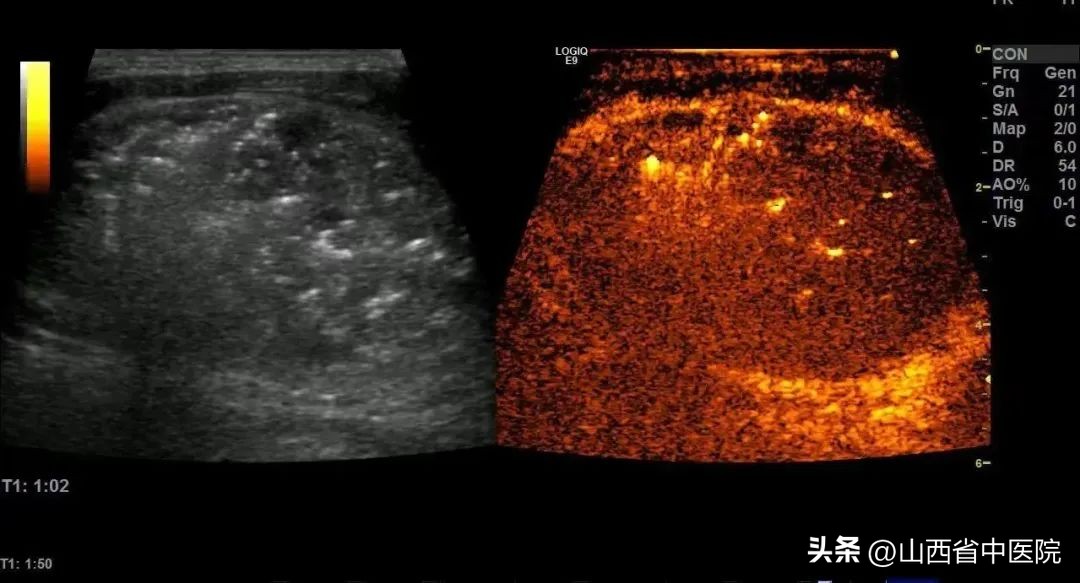

在准备充分的情况下,仅仅半小时左右时间,便完成了该手术,术后超声造影提示结节内部血供消失,消融效果满意。由于热消融脱水等原因,结节术后便明显缩小,术中及术后患者无明显不适。山西省中医院超声诊疗中心完美的完成了本次手术,同时很好的避免了并发症的发生。

(消融后造影,右侧图,结节内部无血流灌注,消融效果满意)